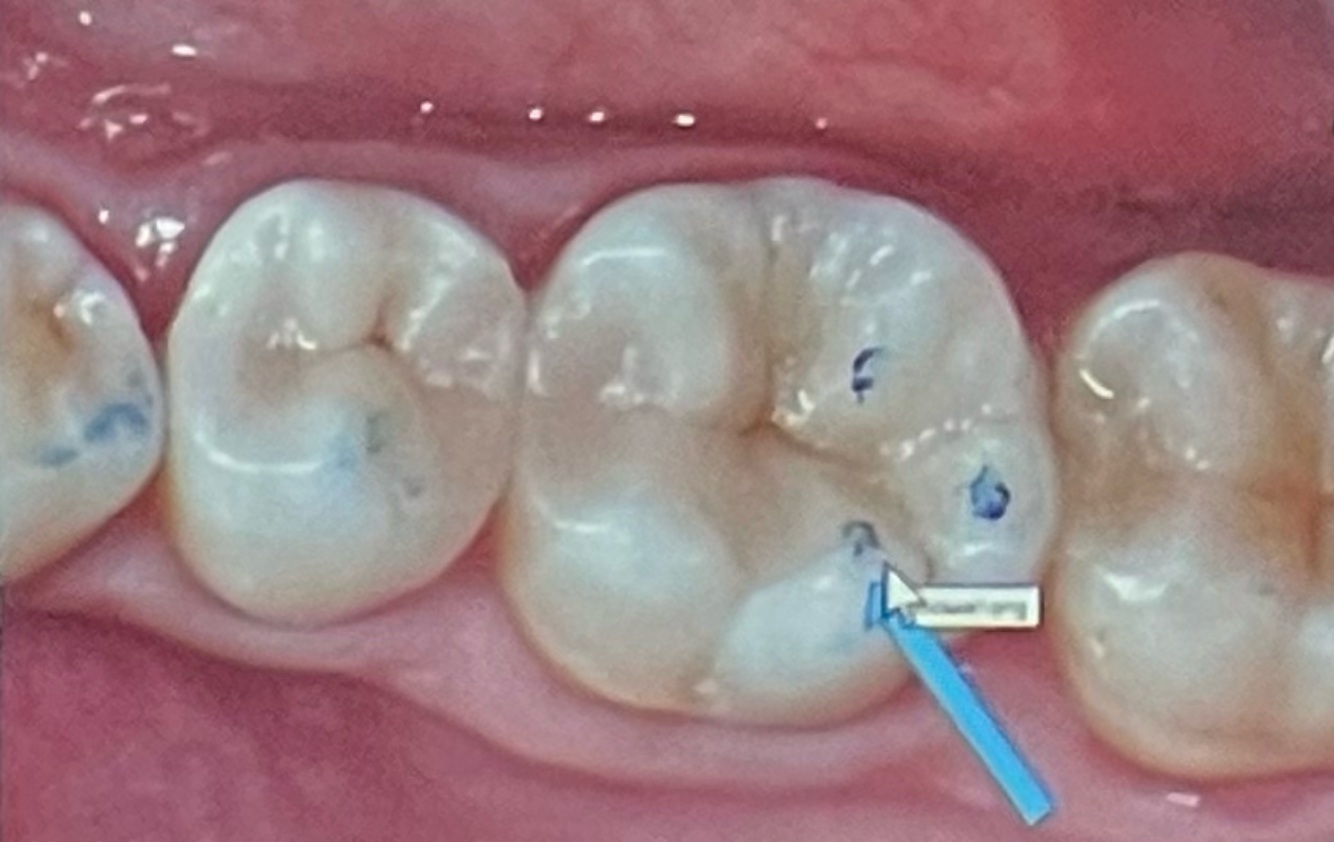

This tooth (indicated by the arrow) is:

16

27

36

47

A